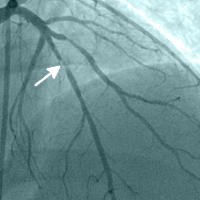

Angiography

During angiography dye is administered through a thin flexible tube (catheter) to the blood vessels that are assessed. With the help of X-ray any occlusions, narrowings or plaques in the arteries can be visualised. Most often the coronary arteries, the aorta and brain arteries are examined with this method. If there is a narrowing or occlusion the vessel can be dilated with various methods, in more severe cases a bypass operation is performed.